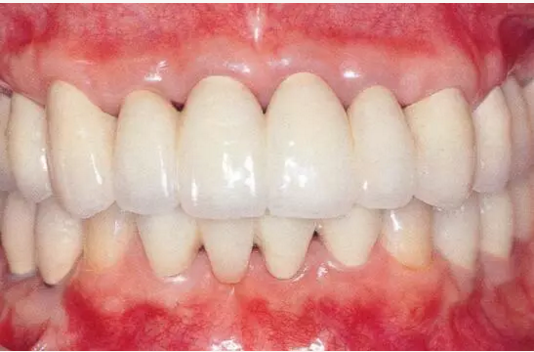

▲圖16-5~7 將左上1和右上1拔除,下頜磨牙區(qū)植入種植體,全口進行牙周外科處理后,佩戴臨時修復(fù)體。圖16-7為佩戴臨時修復(fù)體后的狀態(tài)。由于左上2,3和右上2,3仍然前突,所以覆蓋較深。

切斷左上2,3和右上2,3的連接部,使用活動矯治器進行正畸治療。

▲圖16-11 正畸治療結(jié)束后的研究模型。覆蓋有所改善。

▲圖16-12 佩戴最終修復(fù)體后的狀態(tài)。